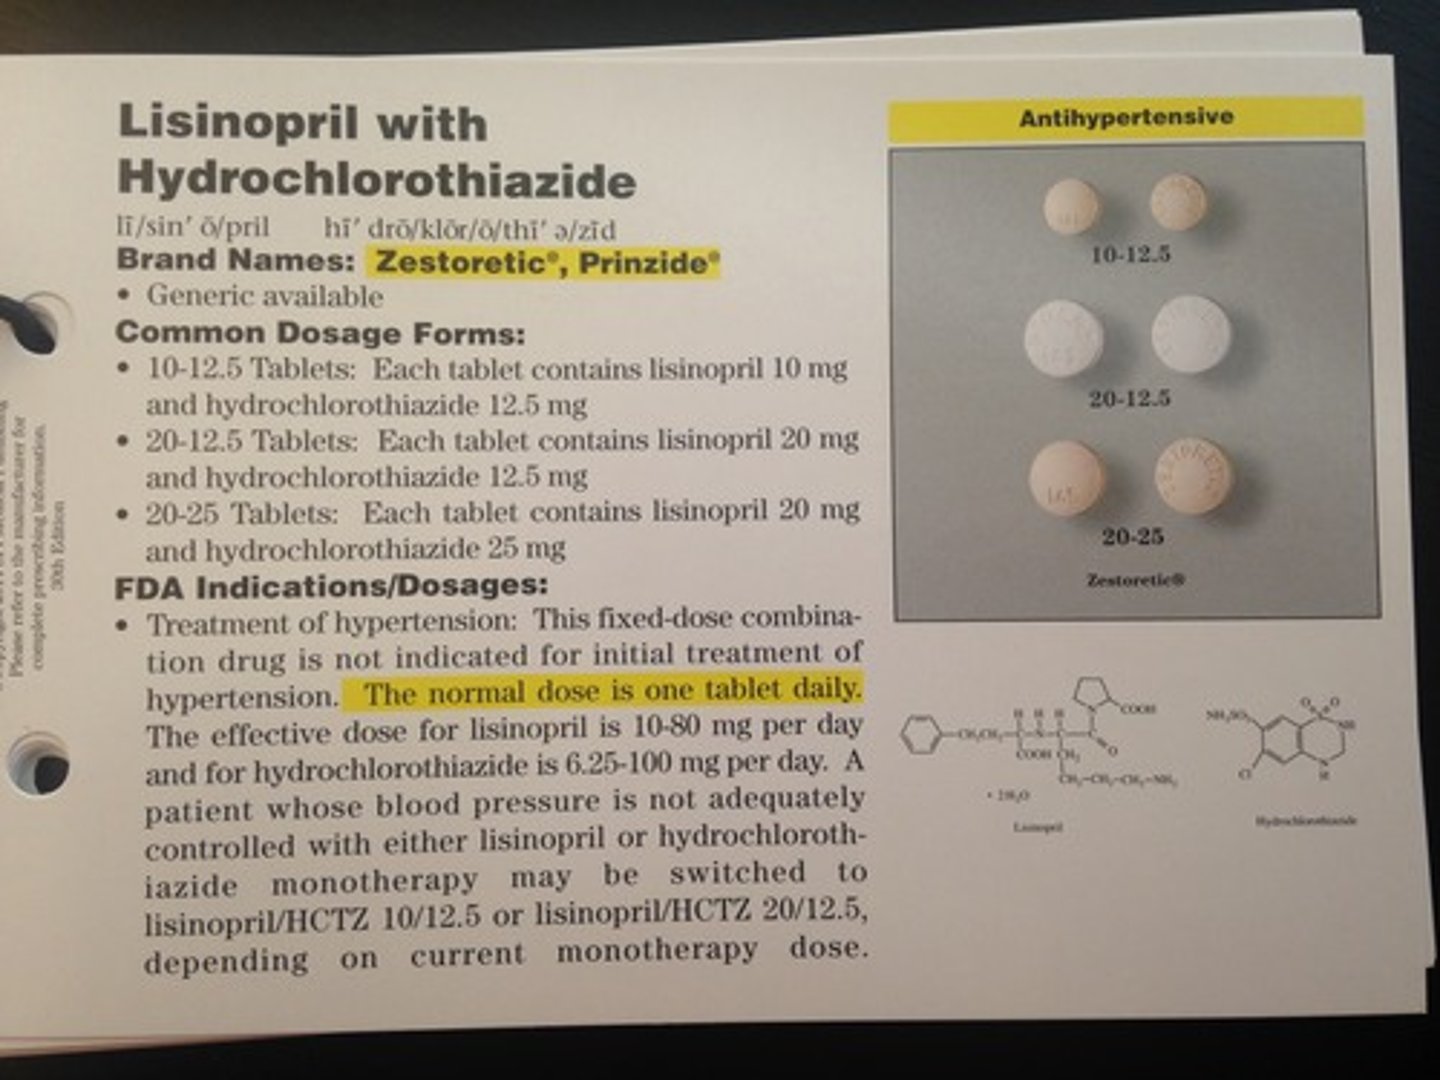

Lisinopril/HCTZ

Brand: Zestoretic

Class: ACEi/Thiazide Diuretic

Drug Interaction: Can increase Digoxin activity

Contraindication: Pregnancy Category D

Indication: Antihypertensives

Schedule: NCLM